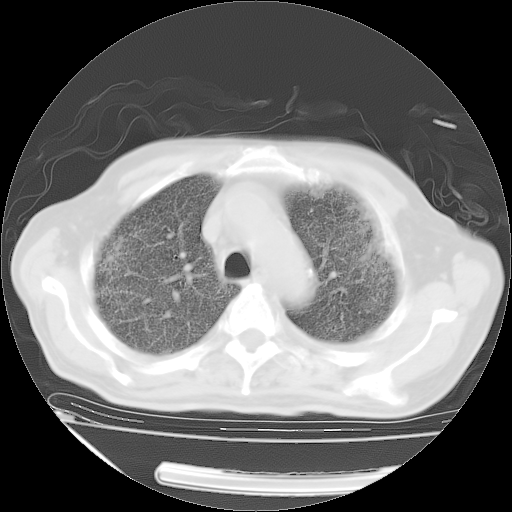

经过24天治疗,岳父的病情基本稳定。生活基本可以自理,可以下床活动。呼吸困难早已消失。体温基本正常。

只是甲强龙用80mg时血小板升到正常,改为60mg后又降到63×10*9/L。

主要治疗甲强龙80mg×14天,60mg×10天;同时抗结核(异烟肼+利福平+乙胺丁醇)。环磷酰胺0.1 tid 10天。

特别感谢胡教授、高管、桃子版主给出关键的治疗建议。桃版把所有肺部影像和全部临床资料请所在医院呼吸科、感染病科、结核科、临床免疫科专家会诊。临床免疫科专家制定了完整的治疗方案。

下一步治疗强地松+环磷酰胺+抗结核。 |